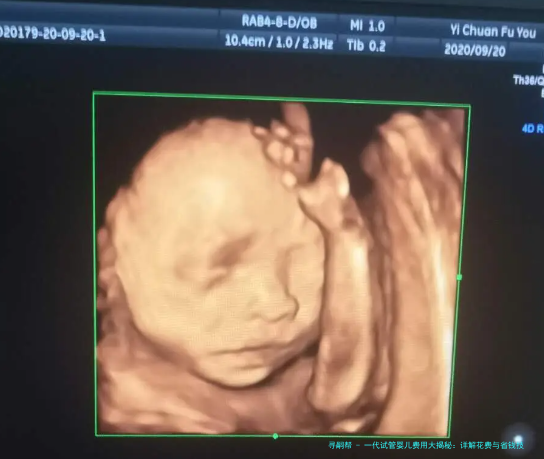

一代试管婴儿,也叫常规体外受精(IVF),是最早的试管婴儿技术,主要适用于女性因素导致的不孕,比如输卵管堵塞或排卵障碍。简单来说,它就是将卵子和精子在实验室里结合,形成胚胎后再移植回子宫。这项技术相对成熟,但费用往往因医疗复杂程度而波动。你知道吗?在中国,一代试管的普及率很高,但费用信息却常常让患者感到困惑,这正是我们需要探讨的。